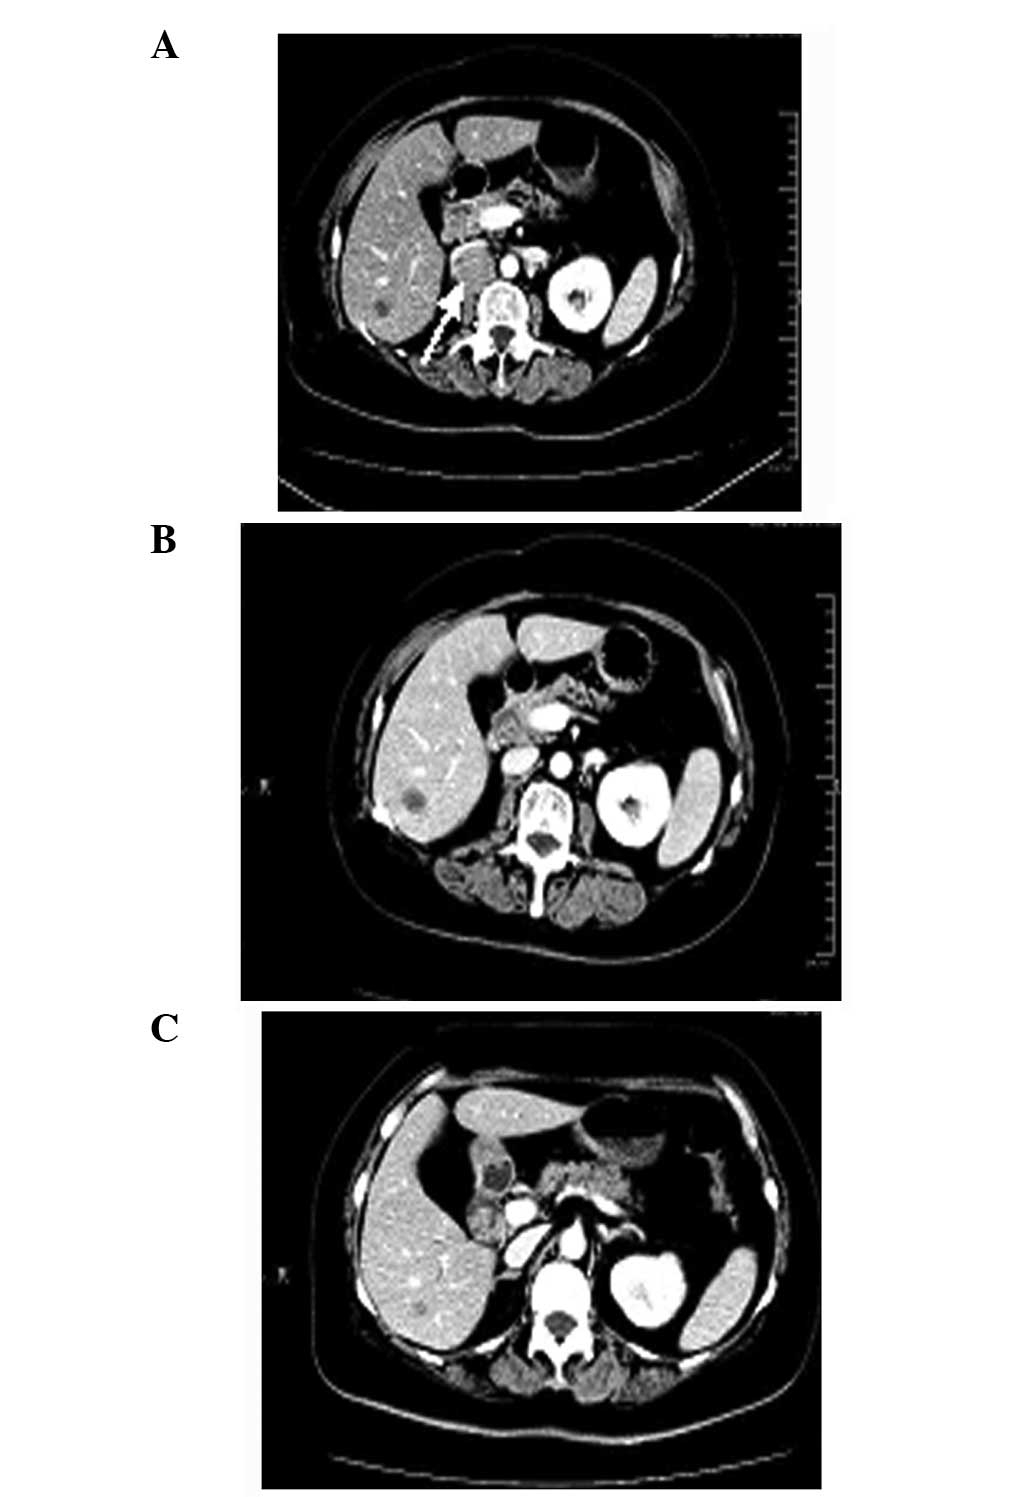

A 65-year-old female presented with right-sided back pain that had been present for one month. The patient had no significant past medical or family history of disease. The physical examination was normal, and laboratory test results showed normal liver function, electrolytes, carcinoembryonic antigen and carbohydrate antigen 19-9. The patient provided written informed consent. A computed tomography (CT) scan of the abdomen revealed a mass measuring ~5×4 cm in the right ureter, with light hydronephrosis (Fig. 1). A chest CT was also reviewed and no primary or metastatic lung lesions were revealed. The patient underwent a right nephroureterectomy and a mass was found within the wall of the right ureter, with grossly negative surgical margins. The microscopic examination showed that the tumor was composed of small cells (Fig. 2). The immunohistochemical staining for the tumor cells was positive for cluster of differentiation (CD)56 (Fig. 3A), chromogranin A (CgA; Fig. 3B) and synaptophysin (Syn; Fig. 3C). Moreover, the tumor expressed high mitotic activity of >20 mitoses per 2 mm2, and the Ki-67/MiBi index was 67% (Fig. 3D). The patient was diagnosed with small cell neuroendocrine carcinoma of the ureter. The post-operative recovery of the patient was uncomplicated, but the patient returned 4 months later, with CT scans revealing recurrences in the retroperitoneum (Fig. 4A). Chemotherapy was administered and following 80 mg/m2 intravenous irinotecan on days 1 and 8 and 25 mg/m2 cisplatin on days 1–3, every 21 days for 4 cycles, CT scans showed a considerably smaller tumor (Fig. 4B). During the regular follow-up examinations, the tumor remained stable (Fig. 4C).

Figure 4

CT scan revealing (A) local recurrences in the retroperitoneum and (B) a considerably smaller tumor following chemotherapy with 80 mg/m2 intravenous irinotecan on days 1 and 8 and 25 mg/m2 cisplatin on days 1–3, every 21 days for 4 cycles. (C) The tumor was stable during the regular follow-up examinations. CT, computed tomography.